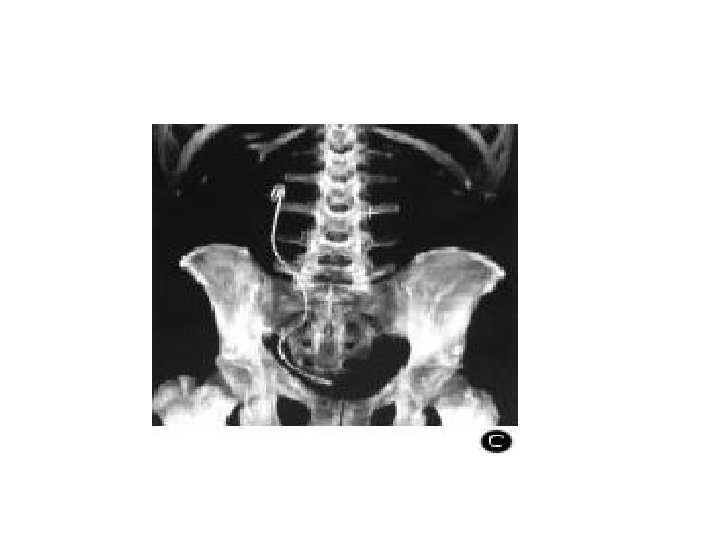

IRA OBSTRUCTIVE • Obstacle sur la voie excrétrice • En cas d’obstacle « haut » , l’IRA n’apparaît que si l’obstacle est bilatéral ou sur rein unique • En cas d’obstacle « bas » , il existe le plus souvent un globe vésical

haut bas

Causes IRA obstructive • Lithiases urinaires sur rein unique (sujet jeune) • Pathologie tumorale: (sujet âgé) • Adénome, cancer de la prostate • Tumeur de vessie • Cancer du rectum, utérus, ovaire envahissant les voies excrétrices • Pathologie inflammatoire: fibrose rétro-péritonéale

• IRA obstructive: • Hématurie, douleur lombaire en cas de lithiase • Dysurie, pollakiurie, en cas de pathologie prostatique • Il faut recher: – Un globe vésical – Un blindage pelvien au toucher vaginal ou rectal

• L’échographie rénale – Met en évidence une dilatation des cavités rénales – Recherche la cause le l’IRA (lithiase, tumeur) • Alternative à l’échographie: uroscanner sans injection

• Traitement: • Urgence medico chirurgicale Drainage d rainer les urines retenues en amont de l’obstacle si globe vésical: sondage urinaire ou cathétérisme sus pubien Si obstruction du haut appareil: montée d’une sonde JJ ou néphrostomie per cutanée • Syndrome de lève d’obstacle